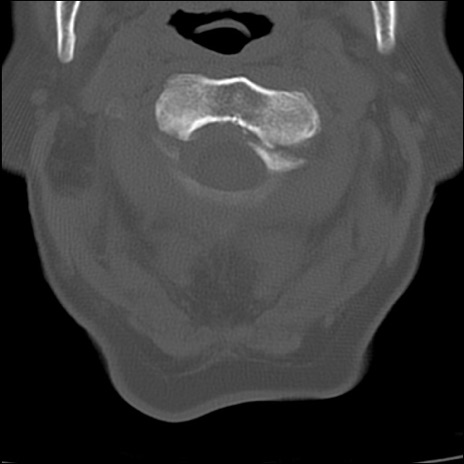

症例48 頚椎CT(横断像)

頚椎CT